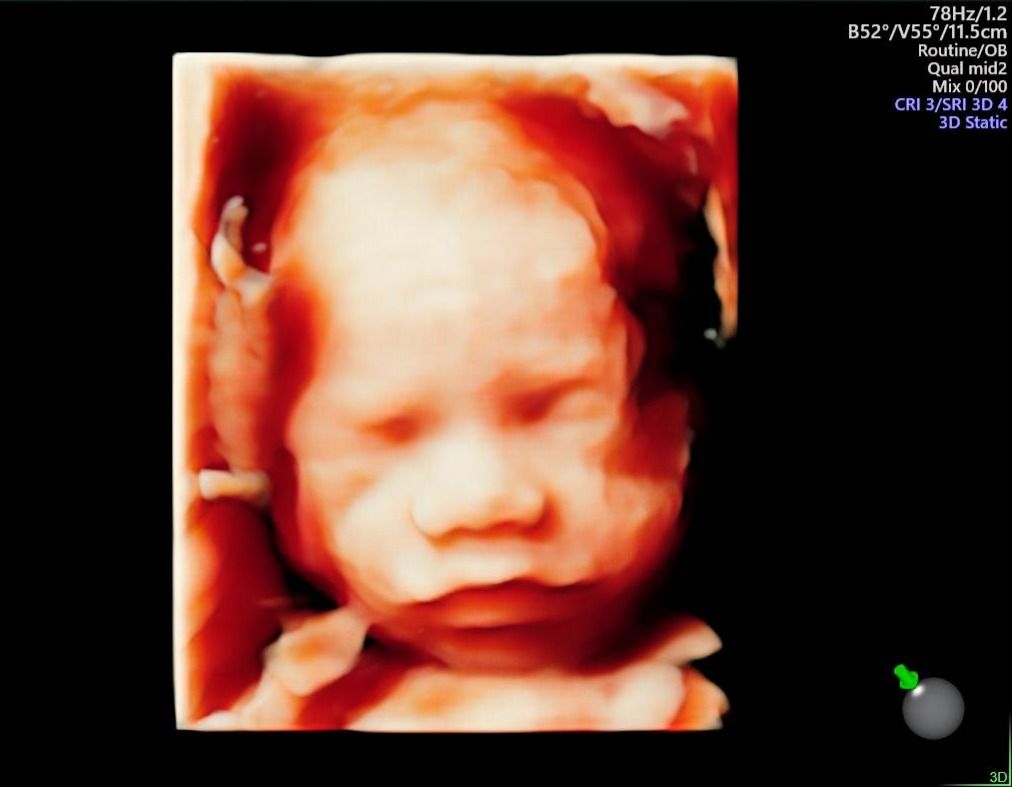

Nel corso della mia lunga esperienza lavorativa in ospedale,  ho maturato una particolare competenza nella gestione delle gravidanze a rischio sia per problematiche materne che fetali, nella diagnostica prenatale sia invasiva ( amniocentesi, villocentesi) con all'attivo migliaia di procedure effettuate, che nella diagnostica strumentale ecografica ( ecografie ostetriche di I e II livello, test combinato, studio della Translucenza nucale, DNA fetale, studio doppler flussimetrico dei distretti materni e fetali ).

Foto e video